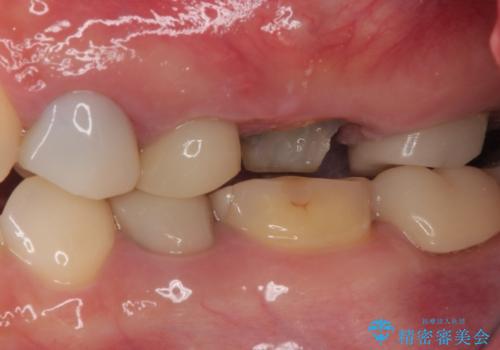

- 奥歯のクラウンが土台ごと外れてしまったとのことで来院された患者様です。

保存可能ではありましたが、予後不良と患者様ご自身が判断されており、相談の結果抜歯即時埋入インプラントによる補綴治療を行うこととしました。

垂直方向への炎症が大きく、抜歯即時埋入はできたものの、即時荷重(インプラント埋入時の仮歯の装着)を可能とする安定値は得られませんでした。

それにもかかわらず、僅か4ヶ月で治療を終えることができ、以前の上顎洞底の挙上を行っていた頃よりも半年以上短縮することができました。